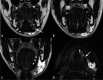

Inflammatory and obstructive disorders of the salivary glands are caused by very different pathological conditions affecting the gland tissue and/or the excretory system. The clinical setting is essential to address the appropriate diagnostic imaging work-up. According to history and physical examination, four main clinical scenarios can be recognised: (1) acute generalised swelling of major salivary glands; (2) acute swelling of a single major salivary gland; (3) chronic generalised swelling of major salivary glands, associated or not with "dry mouth"; (4) chronic or prolonged swelling of a single major salivary gland. The algorithm for imaging salivary glands depends on the scenario with which the patient presents to the clinician. Imaging is essential to confirm clinical diagnosis, define the extent of the disease and identify complications. Imaging techniques include ultrasound (US), computed tomography (CT) and magnetic resonance (MR) with MR sialography.